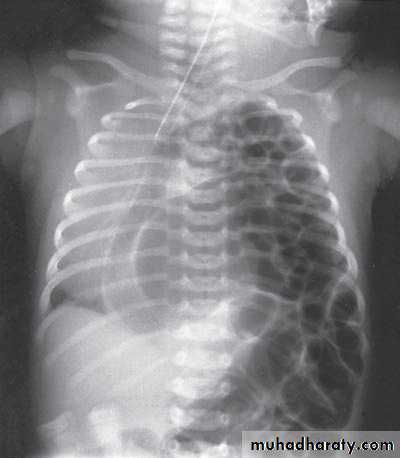

Scaphoid abdomen

content